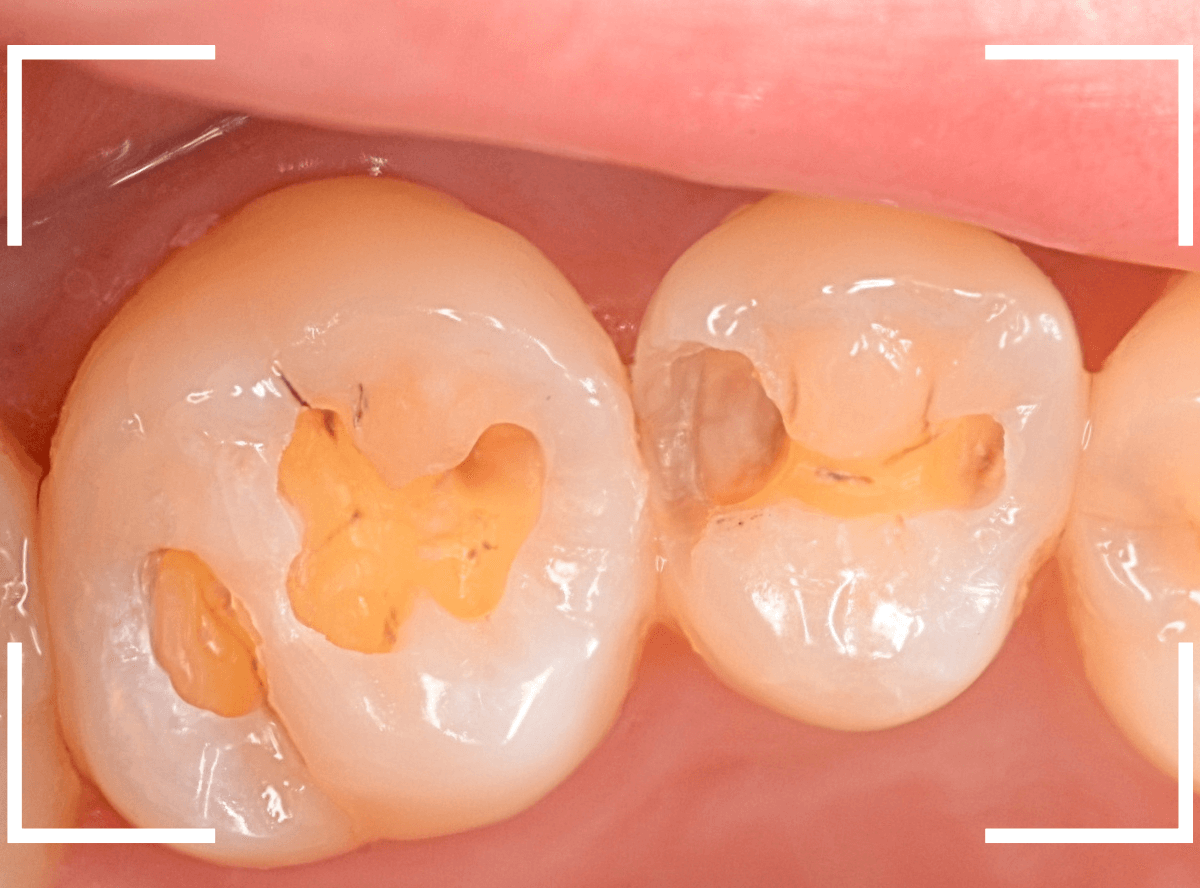

Case.17 レントゲンにはっきり写らないレジンの中の虫歯を削って調べる2

今回も、下の奥歯の虫歯を治療した例です。

特に症状はありませんが、以前に治療したレジンが劣化してすり減っているのと、少し中が黒く透けて見えて、虫歯になっているのが怪しいです。

青いラインが歯の神経です。

以前の虫歯が深めだったようで、レジンが深めにつめてあるのがわかります。

その下がうっすらと虫歯っぽい影になっています(赤いライン)。

虫歯になっているか微妙なラインですが、レジンも劣化していますので、患者さんにご説明して治療することになりました。

レントゲンで虫歯と思われる部分をレジンを除去しました。

見た目には虫歯かどうかはっきりわかりません。

う蝕検知液で染め出します。

うっすらと赤く染色されました。

レントゲン写真と同じく、レジンの下で静かに虫歯が進行し始めていたようです。

もともと深めの虫歯だった部分なので、早いうちに治療が進められてよかったです。

全てのレジンと虫歯を除去しました。

お薬をつめて、症状が出ないかしばらく経過観察します。

歯の外壁部分も薄くなってますので、レジンでは長期保存は難しいと思われます。

今回は、インレーで最終修復する予定です。